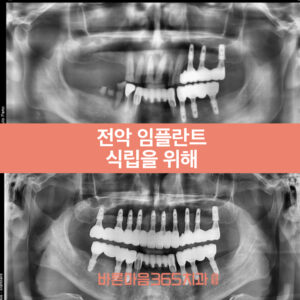

울산삼산동치과, 전악 임플란트 식립을 위해

울산삼산동치과, 전악 임플란트 식립을 위해   안녕하세요.   울산삼산동치과 바른마음365치과 박완규 김도희 원장입니다.   오늘은 울산삼산동치과 전악 임플란트를 식립한 케이스 보여드리겠습니다.   바로 엑스레이 사진과 임상 사진을 보시죠.     예전에 식립한 왼쪽 위아래 임플란트는 잘 되어 있으나 오른쪽 위아래 어금니가 없거나 뿌리만 남아있고,   위아래 앞니들은 치주염으로 인해 심한 더보기…